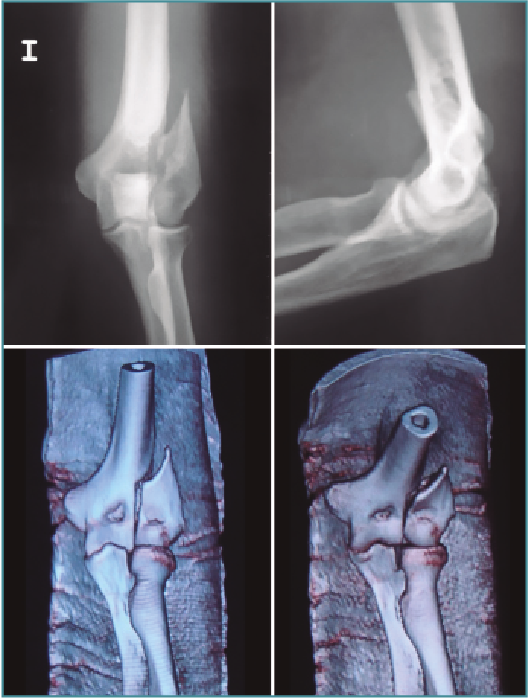

Fractura unicondílea del húmero

Las fracturas del húmero unicondilar distal a veces son susceptibles de una evaluación y fijación asistida artroscópicamente. Esto es particularmente cierto cuando no hay conminución presente.

Las fracturas del cóndilo humeral de tipo I, sin embargo, son más pequeñas y afectan mucho menos la estabilidad de la articulación del codo. Algunos investigadores recomiendan el manejo no quirúrgico de estas fracturas, pero las desventajas del tratamiento no quirúrgico incluyen la incongruencia de la articulación residual, la inmovilización prolongada y la posibilidad de desplazamiento tardío de los fragmentos de fractura(9).

También se ha recomendado la reducción abierta y la fijación interna para las fracturas desplazadas de Milch de tipo I(10).

Fractura supraintercondílea del húmero

Las fracturas supracondíleas también requieren una reconstrucción con tornillos y placas, y una artrotomía en la mayoría de los casos. Las fracturas supracondíleas se dividen en 2 tipos: en extensión (la mayoría) y en flexión.

Las fracturas que se presentan con una mínima inflamación son susceptibles de fijación artroscópica asistida. El hematoma y los restos articulares se eliminarán y usaremos una o varias AK para reducir la fractura percutáneamente (Figuras 9 a 12) colocando a continuación tornillos canulados en la columnas medial o lateral del húmero. Se debe usar el fluoroscopio para evitar introducirlo dentro de la fosa olecraniana(11).

Figura 9. Radiografías y tomografía axial computarizada de fractura supraintercondílea.

Figura 10. Colocación del paciente, visión articular de la fractura y reducción artroscópica.

Figura 11. Fijación interna con 3 tornillos canulados, control por escopia y artroscópica.

Figura 12. Resultado final.

En el postoperatorio, los pacientes pueden comenzar ejercicios de rango de movimiento protegidos de manera inmediata y así reducir las posibilidades de rigidez postoperatoria asociadas con el tratamiento cerrado de estas fracturas(12).